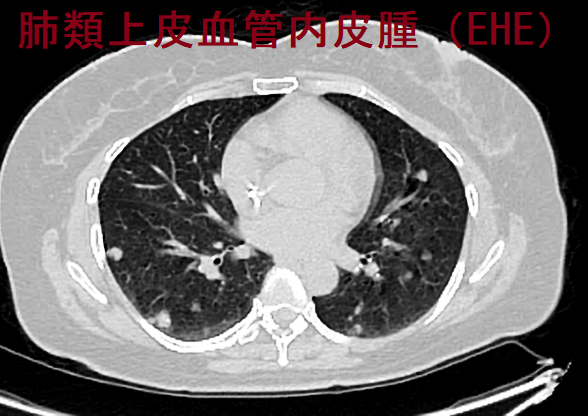

肺類上皮血管内皮腫(EHE)

肺類上皮血管内皮腫(EHE) CT画像(Radiopaediaより改変)

肺類上皮血管内皮腫(EHE; Pulmonary epithelioid hemangioendothelioma)は、肺、肝、軟部組織、骨に発生する稀な腫瘍で、悪性度の報告は様々です。肺に多発性小結節を形成し、甲状腺乳頭癌の多発性肺転移を疑われる事があります。

細胞診では卵円形核を有する軽度異型細胞を認め、血管内皮由来なのでサイログロブリン(Tg)TTF1の免疫染色陰性、血管内皮細胞マーカーのCD34 とFactor VIIIが陽性になります。(第59回 日本甲状腺学会 P2-4-4 甲状腺乳頭癌で肺に多発性小結節を伴い、肺類上皮血管内皮腫(EHE)と診断された1例)

肺類上皮血管内皮腫(EHE)は、

1. ほとんどの患者で肺に限局

2. 骨転移、リンパ節転移、胸膜転移(胸膜肥厚や胸水)もある(甲状腺乳頭癌肺転移の様)

3. 胸部CT画像;両肺多発性結節、ほとんどが直径2.0cm未満、石灰化あり。孤立性結節はまれ(甲状腺乳頭癌肺転移の様)

4. 病理組織所見;不規則な巣状構造を有する好酸性結節が、乳頭状に肺胞腔へ広がる。腫瘍細胞は小異型を伴う類上皮。免疫組織化学的には、CD34、CD31、第VIII因子およびビメンチン(VIM)陽性

5. 標準治療はなく、全生存期間(OS)中央値は4.58年

[Zhonghua Jie He He Hu Xi Za Zhi. 2021 Nov 12;44(11):966-971.]